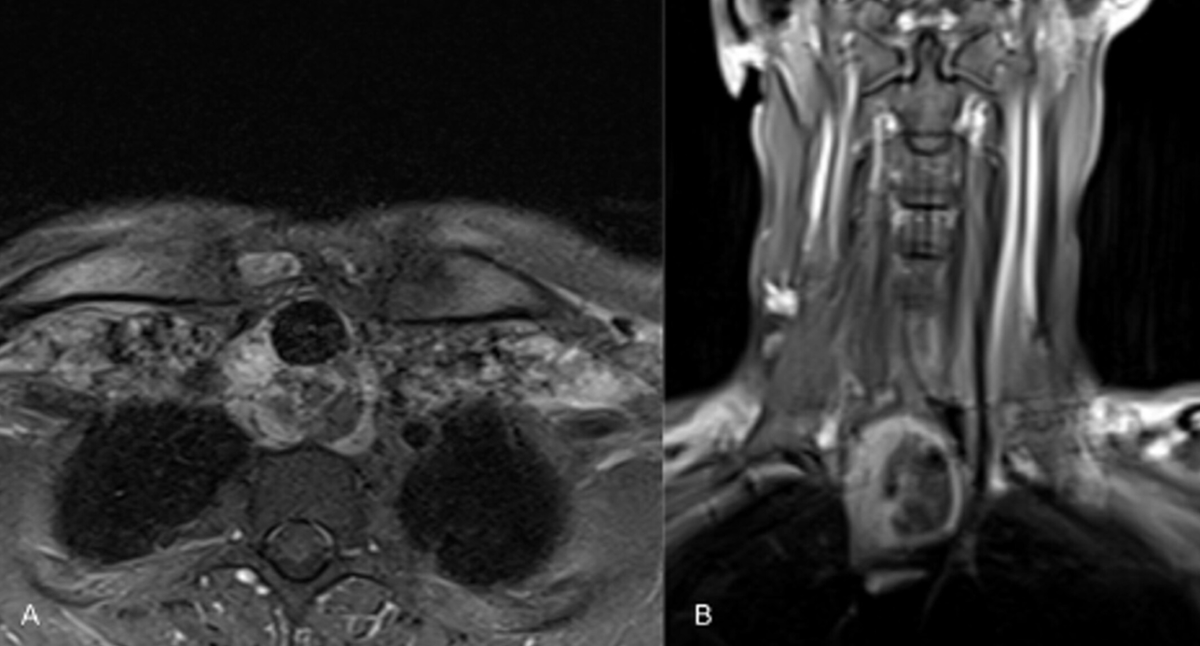

Гистология подтвердила аденокистозный рак. МРТ показала краниокаудальное образование в задней стенке трахеи размером 5,5 см без явного поражения пищевода. Консилиум признал новообразование неоперабельным. Пациент направлен на химиолучевую терапию и молекулярно-генетическое тестирование для оценки возможности таргетного лечения.